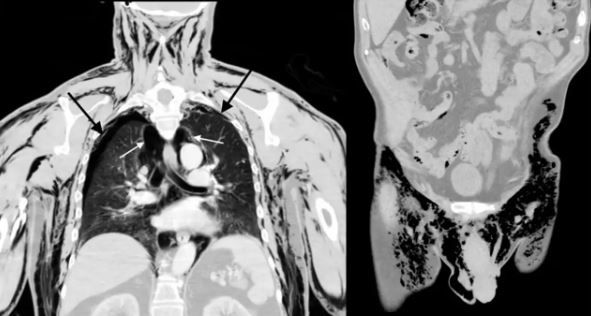

Ein CT-Scan der Brust des 72-jährigen Mannes (links). Die schwarzen Pfeile zeigen die kollabierten Lungen, während die weißen Pfeile auf Lufteinschlüsse (feste schwarze Bereiche) zeigen, die zwischen dem Innenraum außerhalb der Lunge und innerhalb der Brustwand eingeschlossen sind. Der Unterleib des Mannes (rechts) zeigt die Luftmenge (schwarze Bereiche) in seinen Oberschenkeln und seinem Hodensack.